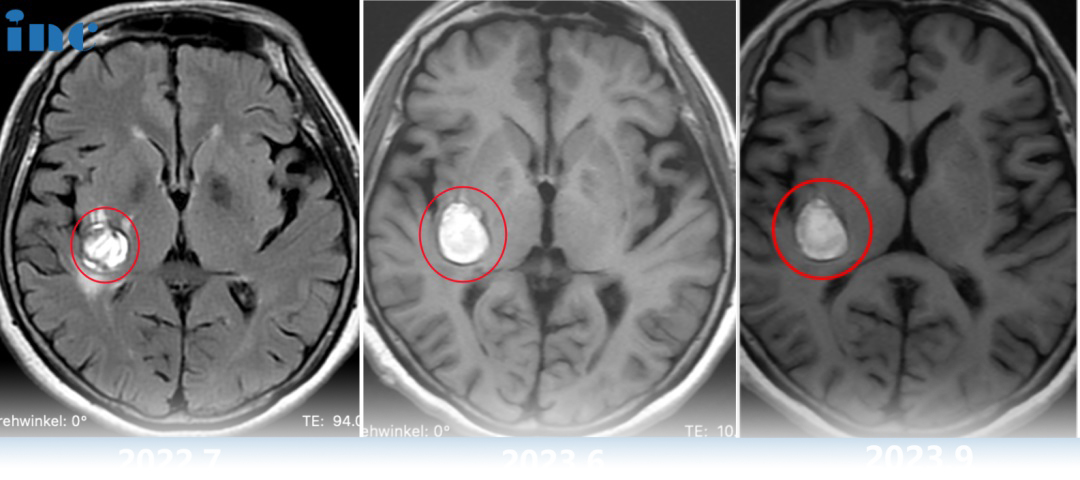

然而谁也没想到9月底教授在华手术期间柯女士症状开始出现波动,发作频繁。2023年9月5号再次核磁,病灶又增大了,除了原来各种麻的症状,我又感觉这个脸、耳朵都疼,麻、胀……症状又加重了。

当巴教授查看核磁图像后,发现病灶较前增大,结合患者病情有进展,告知患者随时会有出血风险,需要立即手术。柯女士和家人与巴教授紧急视频沟通之后,决定提前手术,果断买飞机票来到苏州。9月29日视频会议,30日早晨从东北飞过来,10月1日成功手术。柯女士一家人终于松了一口气,这个困扰他们已久的问题终于得到的解决。

术后核磁显示,海绵状血管瘤得到顺利全切,柯女士的状态也好,神采奕奕,和常人无异。

柯女士仅仅两个月后,9月份2次做头颅核磁平扫和头颅血管成像,报告显示:右侧基底节区含血病灶大小约18*19mm。病灶增大了,那么症状呢,有何变化?